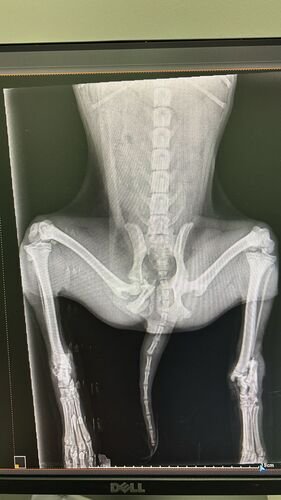

Pantera tem apenas 06 meses de vida e foi vítima de atropelamento e restou poli traumatizada (fraturas expostas nas duas patinhas traseiras, fratura na pelve e na patinha da frente).Seus tutores não tem condições de arcar com todos os custos do tratamento e cirurgias necessárias.